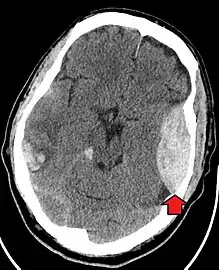

Traumatic brain injury (TBI)

Most patients with more severe traumatic brain injury have of a combination of intracranial injuries, which can include diffuse axonal injury, cerebral contusions, and intracranial bleeding, including subarachnoid hemorrhage, subdural hematoma, epidural hematoma, and intraparenchymal hemorrhage.[8][17] The recovery of brain function following a traumatic injury is highly variable and depends upon the specific intracranial injuries that occur, however there is significant correlation between the severity of the initial insult as well as the level of neurologic function during the initial assessment and the level of lasting neurologic deficits.[17] Initial treatment may be targeted at reducing the intracranial pressure if there is concern for swelling or bleeding within this skull, which may require surgery such as a hemicraniectomy, in which part of the skull is removed.[8][17]